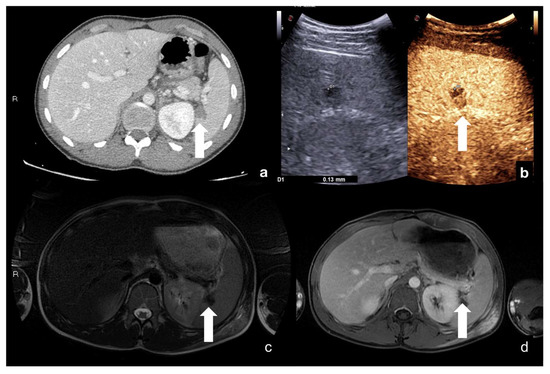

Choose the imaging in your strings (Figure 22).

Figure 22.

Multimodal evaluation of splenic laceration (white arrows) at portal phase CT scan (a), CEUS (b), fat-sat T2w (c), and post-contrast fat-sat T1w MRI (d), with good overlap of findings.